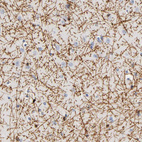

Immunohistochemistry analysis in human cerebral cortex and pancreas tissues using HPA004128 antibody. Corresponding PLP1 RNA-seq data are presented for the same tissues.